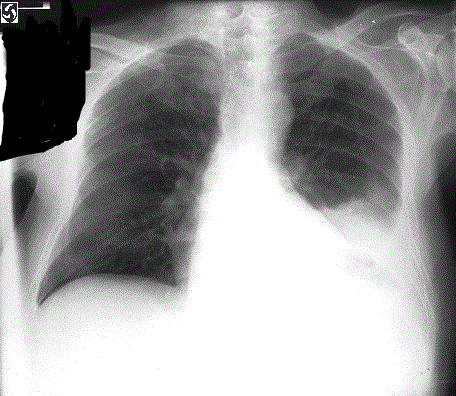

341) A 78 year old man presents with progressively increasing shortness of breath. He has a 100 pack year history of smoking. His past medical history is significant for chronic obstructive pulmonary disease, coronary artery disease and congestive heart failure. He has been admitted several times in the past one year for Congestive heart failure exacerbations which resulted from his non-compliance with diet and medications. His medications include aspirin, metoprolol, enalapril, and spironolactone and tiotropium inhaler. On examination, he is afebrile with respiratory rate 24/min, pulse 106beats/min, blood pressure 140/90. Breath sounds are decreased and there is dullness to percussion on the left side of the chest. Heart sounds are regular and there is no S3 gallop. A 2D echocardiogram reveals ejection fraction at 30% and a brain natriuretic peptide 250 pg/ml (Normal less than 100pg/ml) . An EKG reveals changes consistent with left ventricular hypertrophy. A Chest X-ray is shown below:

Which of the following is the most appropriate next step in management?

A) Intravenous Furosemide

B) Tube Thoracostomy

C) Intravenos Nitroglycerin

D) Needle thoracentesis

E) Implantable Cardioverter-Defibrillator (ICD) placement